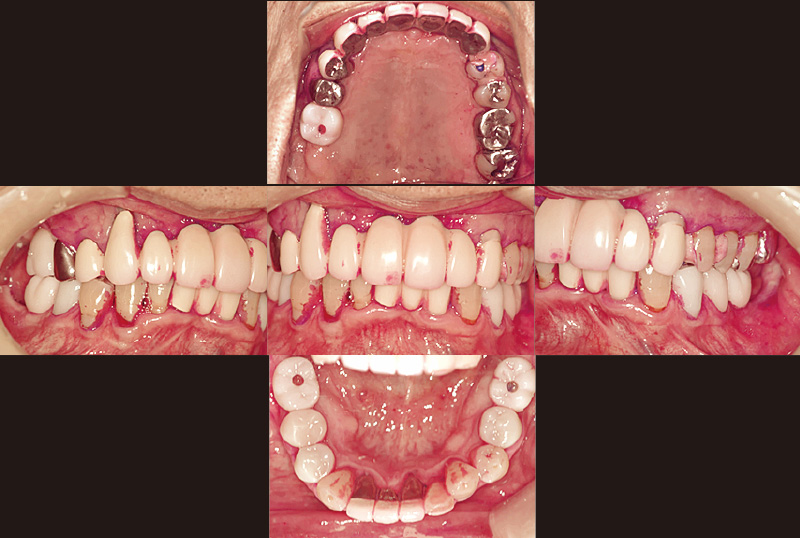

症例の患者さんは、奥様の介護があり毎日忙しくされていることもあってか、とにかくプラークコントロールが不良で、改善の兆しが見えませんでした。初診から6年が経過し、その間補綴治療を行ってきましたが、相変わらず磨き残しは目立っていました(図3)。そのため、染め出し後に「PrimescanConnect」でスキャンしたデータをお見せしたところ、「こんなにも磨き残しがあるとは思ってなかった」と、とても驚かれ、それ以降セルフケアの意識が向上し、磨き残しは大幅に減少しました(図4~6)。

自宅では、以前から電動歯ブラシを使用されていましたが、次の来院時に、「ソニッケアー 6100 プロフェッショナル」(以下:ソニッケアー 6100)をご紹介したところ、「パワーがあってとても良い」と気に入られて、その場で購入されました(図7~9)。私も以前から「ソニッケアー」を使用していましたが、「ソニッケアー 6100」は、従来よりコンパクトで軽量になり、とても持ちやすくなりました。パワーがあるわりに、振動がマイルドで飛散が少なくなったとも感じます。また、従来は臼歯の頰側部にブラシを入れた際に頰粘膜に圧迫されると、少しパワーが落ちる感覚がありましたが、「ソニッケアー6100」では、それも気にならなくなりました。この患者さんには替ブラシに「プレミアムオールインワンブラシ」を選択。購入後にブラシの当て方や動かし方を丁寧に指導し、毎日ご自宅で使用していただいています。

図12 図4から3か月経過後の状態。「ソニッケアー」を継続して使用され、プラークが減り歯肉の腫脹なども改善していることがわかる。